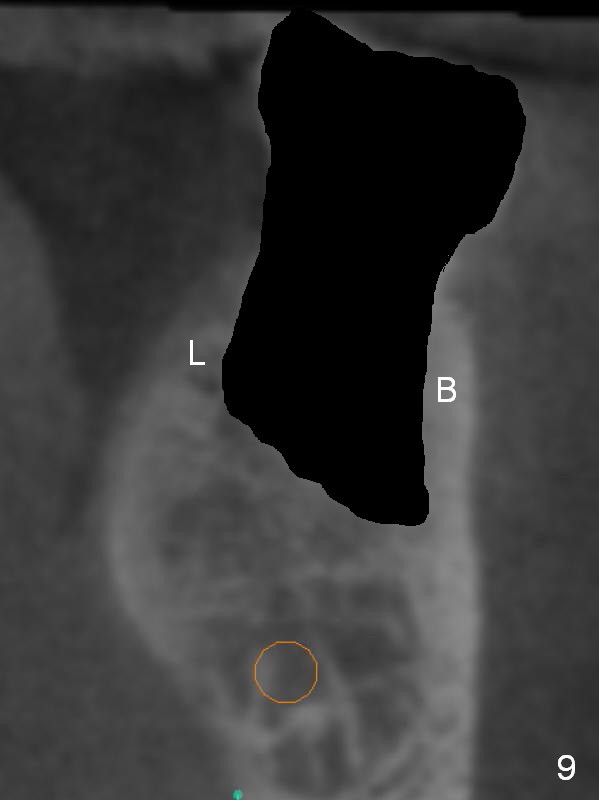

Coronal section through the distal root (Fig.8 D) shows that the lingual plate (Fig.9 (post extraction (Metronidazole)) L) looks thicker than the buccal one (B). When socket shield is performed in the distal root (Fig.10 *, surgical bur block with long surgical fissure bur), there will be less chance to place pressure on the thin buccal plate. The 6.9x10 mm implant may be oversized (Fig.11). Prepare DIO Sinus Master Kit so that 3-4 mm stoppers can be used for osteotomy.